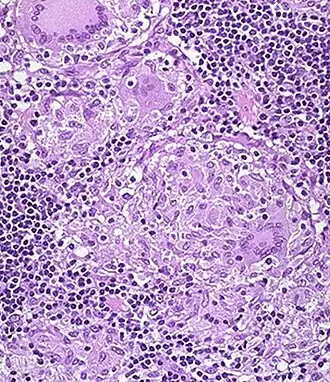

Een niet-necrotiserend granuloom van een patiënt met de Ziekte van Crohn, zoals dat er bij microscopisch weefselonderzoek uit kan zien. Linksboven tegen de rand een meerkernige reuscel | ||||

Een granuloom (meervoud granulomen) is een type ontstekingsreactie dat gezien kan worden bij histologisch onderzoek van weefsels. Het is een afgebakende opeenhoping van histiocyten (macrofagen). Granulomen ontstaan als een opruimreactie, bij deeltjes of micro-organismen die het lichaam niet goed kan verwerken. Een aantal andere kenmerken kunnen aanwezig zijn:

- Soms zijn er ook meerkernige reuscellen, die ontstaan door het vervloeien van een aantal histiocyten. Er ontstaat een grote cel met meerdere celkernen. Hiervan zijn weer verschillende types te onderscheiden, zoals vreemdlichaamstype en Toutonse reuscellen.

- Vaak zijn er behalve histiocyten ook lymfocyten en plasmacellen te vinden.